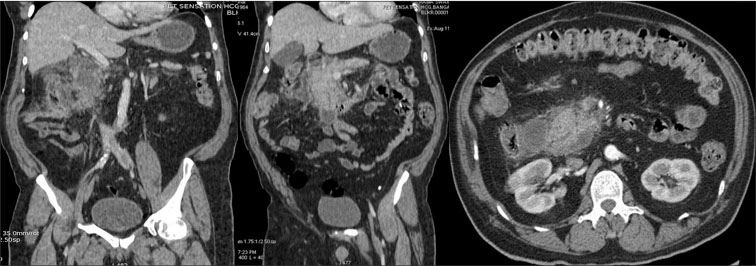

|?Figure. 1? The head of pancreas is bulky with moderate peripancreatic fat stranding, multiple heterogeneous attenuating peripancreatic, and paraduodenal areas with focal internal fat attenuation?suggestive of acute focal pancreatitis with multiple peripancreatic and paraduodenal necrotic collections. There was no evidence of ascites or vascular complications. The modified computed tomography severity index was four|